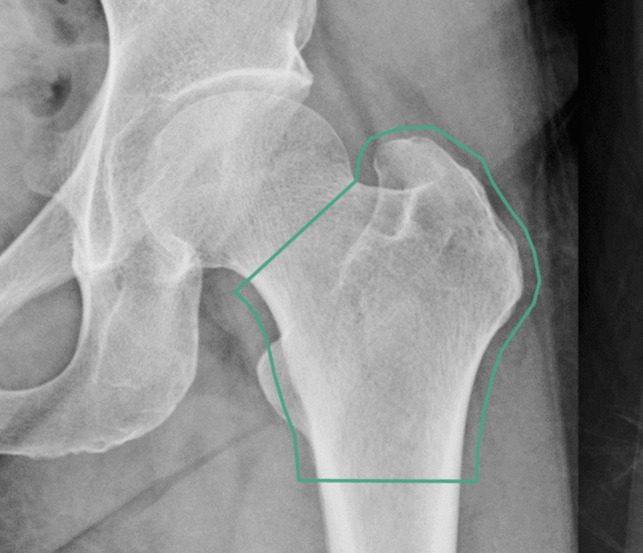

Purpose: This study aimed to evaluate the diagnostic accuracy, reproducibility, and robustness of OsteoSight™, an automated image analysis tool designed to identify low bone mineral density (BMD) from routine hip and pelvic X-rays. Given the global rise in osteoporosis-related fractures and the limitations of current diagnostic paradigms, OsteoSight offers a scalable solution that integrates into existing clinical workflows.

Methods: Performance of the technology was tested across three key areas: (1) diagnostic accuracy in identifying low BMD as compared to dual-energy X-ray absorptiometry (DXA), the clinical gold standard; (2) reproducibility, through analysis of two images from the same patient; and (3) robustness, by evaluating the tool's performance across different patient demographics and X-ray scanner hardware.

Results: The diagnostic accuracy of OsteoSight for identifying patients at risk of low BMD was area under the receiver operating characteristic curve (AUROC) 0.834 [0.789-0.880], with consistent results across subgroups of clinical confounders and X-ray scanner hardware. Specificity 0.852 [0.783-0.930] and sensitivity 0.628 [0.538-0.743] met pre-specified acceptance criteria. The pre-processing pipeline successfully excluded unsuitable cases including incorrect body parts, metalwork, and unacceptable femur positioning.